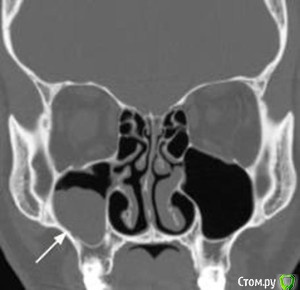

Kostoprav Опубликовано 26 апреля, 2015 Поделиться Опубликовано 26 апреля, 2015 Всем доброго времени суток коллеги!Проблема в следующем- высокая септа и мукоцеле на медиальной стенке пазухи.Мой план: сделать два окна в пазуху по обе стороны от перегородки, аккуратно попробовать отслоить слизистую и если получиться не порвать ее установить два болта не трогая кисту. В случае тотального разрыва мембраны спилить перегородку, убрать мукоцеле, зашить пазуху и повторно пойти на синуслифт через 2 месяца.Хотелось бы услышать Ваши варианты дорогие коллеги. 1 Ссылка на комментарий

Alexey Doc Опубликовано 26 апреля, 2015 Поделиться Опубликовано 26 апреля, 2015 Покажите пожалуйста соустье справа. На этих срезах видно только слева Ссылка на комментарий

Kostoprav Опубликовано 26 апреля, 2015 Автор Поделиться Опубликовано 26 апреля, 2015 (изменено) соустье работает Изменено 26 апреля, 2015 пользователем Kostoprav Ссылка на комментарий

Bier Опубликовано 28 апреля, 2015 Поделиться Опубликовано 28 апреля, 2015 все хорошо, кроме диагноза, это не мукоцелле ) Ссылка на комментарий

kriokov Опубликовано 28 апреля, 2015 Поделиться Опубликовано 28 апреля, 2015 а что? ретенционая 1 Ссылка на комментарий

Bier Опубликовано 30 апреля, 2015 Поделиться Опубликовано 30 апреля, 2015 По цитирую: "мукоцеле отличается более агрессивным ростом с разрушением костных стенок и прорастанием в окружающие ткани, часто в глазницу. Химический состав жидкости при мукоцеле, при одонтогенной кисте и при ретенционной кисте различен. Так же, как и структура кистозных стенок." Нина Каграманян "Мне часто приходится объяснять разницу между мукоцеле и ретенционной кистой, а эта разница принципиальна. Действительно, мукоцеле - это образование с агрессивным ростом, которое деформирует стенки пазух либо разрушает, прорастая в соседние анатомические области. Наиболее частая локализация - лобная пазуха. Основная причина формирования мукоцеле - блок соустья пазухи + операция в синоназальной области в анамнезе. Основное лечение мукоцеле - хирургическая марсупиализация."Ксения Клименко "Это проблема перевода. В англоязычных источниках ретенционные кисты часто называют mucocele, а по-русски это совершенно разные вещи." Игорь Горбоносов "Игорь, на самом деле путаница и среди зарубежных авторов встречается. Есть понятие mucocele, а есть mucous retention pseudocyst." Ксения Клименко 7 Ссылка на комментарий